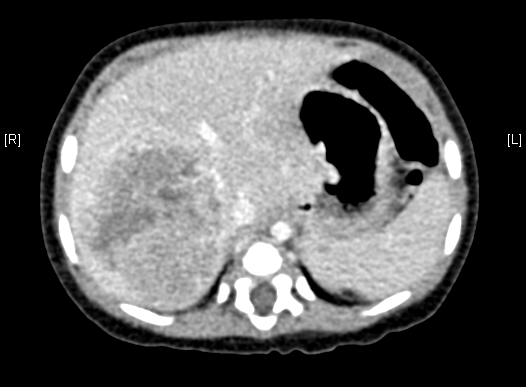

上腹部增强CT:肝右叶巨大占位,肝母细胞瘤可考虑。

术前CT检查:

动脉期

静脉期

平衡期